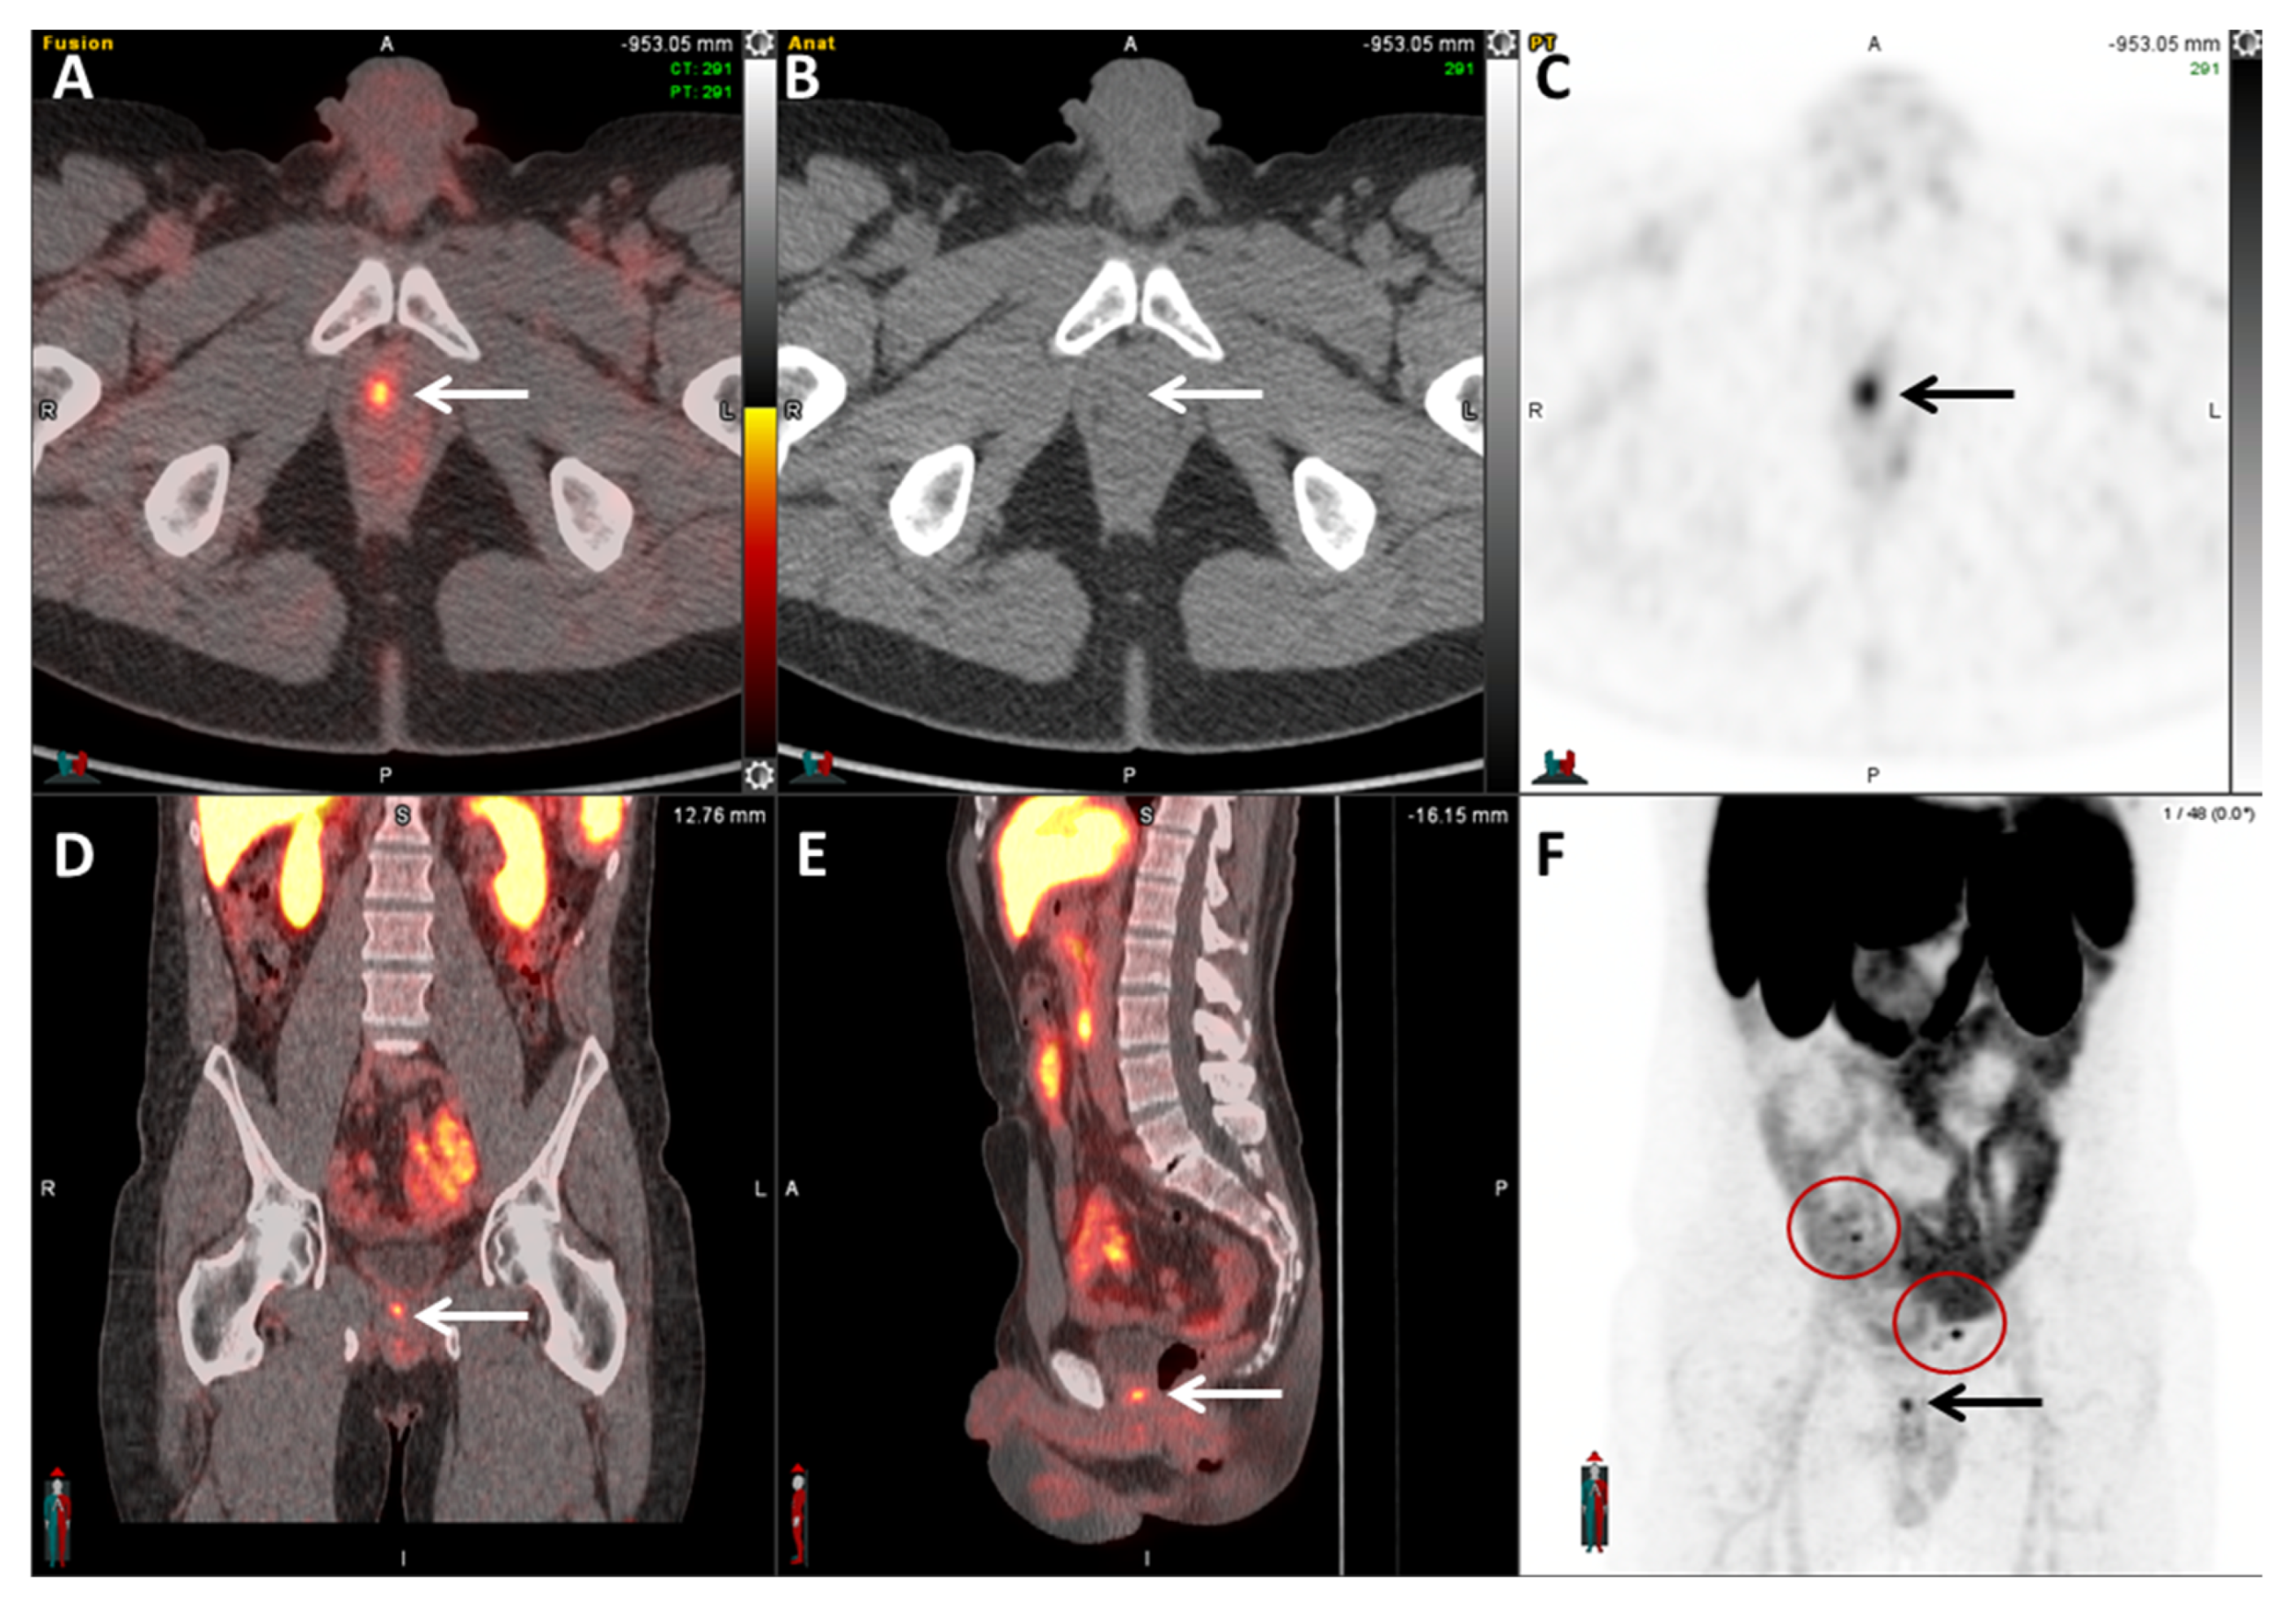

2.5.1. 68Ga-PSMA-11

- Rauscher, I.; Maurer, T.; Fendler, W.P.; Sommer, W.H.; Schwaiger, M.; Eiber, M. 68Ga-PSMA ligand PET/CT in patients with prostate cancer: How we review and report. Cancer Imaging 2016, 16, 14. [Google Scholar] [CrossRef]

- Hofman, M.S.; Hicks, R.J.; Maurer, T.; Eiber, M. Prostate-specific Membrane Antigen PET: Clinical Utility in Prostate Cancer, Normal Patterns, Pearls, and Pitfalls. Radiographics 2018, 38, 200–217. [Google Scholar] [CrossRef]

- Maurer, T.; Gschwend, J.E.; Rauscher, I.; Souvatzoglou, M.; Haller, B.; Weirich, G.; Wester, H.J.; Heck, M.; Kubler, H.; Beer, A.J.; et al. Diagnostic Efficacy of 68Gallium-PSMA Positron Emission Tomography Compared to Conventional Imaging for Lymph Node Staging of 130 Consecutive Patients with Intermediate to High Risk Prostate Cancer. J. Urol. 2016, 195, 1436–1443. [Google Scholar] [CrossRef]

- Perera, M.; Papa, N.; Christidis, D.; Wetherell, D.; Hofman, M.S.; Murphy, D.G.; Bolton, D.; Lawrentschuk, N. Sensitivity, Specificity, and Predictors of Positive 68Ga-Prostate-specific Membrane Antigen Positron Emission Tomography in Advanced Prostate Cancer: A Systematic Review and Meta-analysis. Eur. Urol. 2016, 70, 926–937. [Google Scholar] [CrossRef]

- Calais, J.; Ceci, F.; Eiber, M.; Hope, T.A.; Hofman, M.S.; Rischpler, C.; Bach-Gansmo, T.; Nanni, C.; Savir-Baruch, B.; Elashoff, D.; et al. 18F-fluciclovine PET-CT and 68Ga-PSMA-11 PET-CT in patients with early biochemical recurrence after prostatectomy: A prospective, single-centre, single-arm, comparative imaging trial. Lancet Oncol. 2019, 20, 1286–1294. [Google Scholar] [CrossRef]

- Pienta, K.J.; Gorin, M.A.; Rowe, S.P.; Carroll, P.R.; Pouliot, F.; Probst, S.; Saperstein, L.; Preston, M.A.; Alva, A.S.; Patnaik, A.; et al. A Phase 2/3 Prospective Multicenter Study of the Diagnostic Accuracy of Prostate Specific Membrane Antigen PET/CT with 18F-DCFPyL in Prostate Cancer Patients (OSPREY). J. Urol. 2021, 206, 52–61. [Google Scholar] [CrossRef]

- Morris, M.J.; Rowe, S.P.; Gorin, M.A.; Saperstein, L.; Pouliot, F.; Josephson, D.; Wong, J.Y.C.; Pantel, A.R.; Cho, S.Y.; Gage, K.L.; et al. Diagnostic Performance of 18F-DCFPyL-PET/CT in Men with Biochemically Recurrent Prostate Cancer: Results from the CONDOR Phase III, Multicenter Study. Clin. Cancer Res. Off. J. Am. Assoc. Cancer Res. 2021, 27, 3674–3682. [Google Scholar] [CrossRef]

- Ulaner, G.A.; Thomsen, B.; Bassett, J.; Torrey, R.; Cox, C.; Lin, K.; Patel, T.; Techasith, T.; Mauguen, A.; Rowe, S.P.; et al. 18F-DCFPyL PET/CT for Initially Diagnosed and Biochemically Recurrent Prostate Cancer: Prospective Trial with Pathologic Confirmation. Radiology 2022, 305, 419–428. [Google Scholar] [CrossRef]

- Rowe, S.P.; Macura, K.J.; Mena, E.; Blackford, A.L.; Nadal, R.; Antonarakis, E.S.; Eisenberger, M.; Carducci, M.; Fan, H.; Dannals, R.F.; et al. PSMA-Based [18F]DCFPyL PET/CT Is Superior to Conventional Imaging for Lesion Detection in Patients with Metastatic Prostate Cancer. Mol. Imaging Biol. 2016, 18, 411–419. [Google Scholar] [CrossRef] [PubMed]